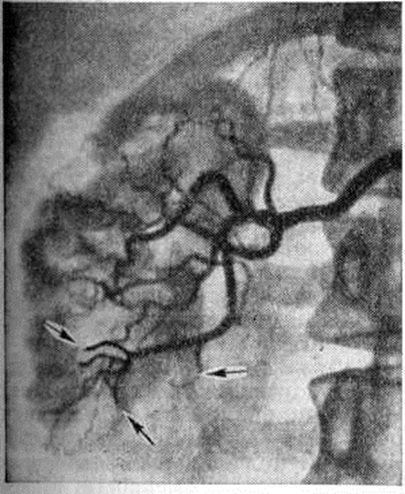

Гнойные очаги в верхнем полюсе почки приводят к ограничению подвижности диафрагмы, появлению выпота в плевральной полости, резкому ограничению подвижности поражённой почки (рисунок 1).

Рис. 1.

Двусторонняя ретроградная уретеропиелограмма при левостороннем гнойном пиелонефрите (снимок сделан с двумя экспозициями — на вдохе и выдохе): справа видны две тени лоханок и чашечек. отражающие их положение на выдохе (1) и вдохе (2), слева — одна тень (ограничение подвижности почки).